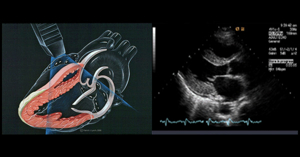

- 심장 초음파 검사

- 경흉부 심장초음파는 별도의 금식이나 준비가 필요 없으며, 검사복으로 갈아입고 검사합니다.

- 경식도 심장초음파나 약물부하 심장초음파는 검사 전 금식 및 약 복용 관련 별도의 지시가 있을 수 있습니다.